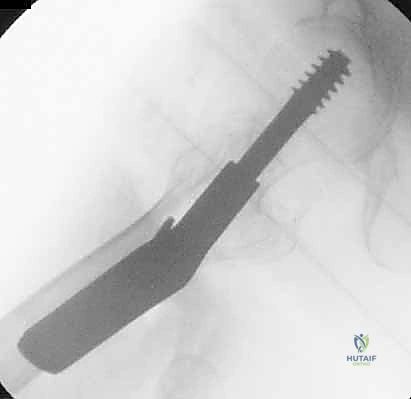

4. إدخال السلك الدليلي (Guide Wire)

يتم إدخال سلك معدني رفيع جداً عبر العظم باتجاه رأس الفخذ تحت توجيه الأشعة المستمر. هذا السلك يعمل كمسار دقيق سيتبعه المسمار النهائي. يجب أن يكون السلك في الموضع الهندسي المثالي لتجنب اختراق مفصل الورك.

5. الحفر وتثبيت الغرسة (Reaming and Implantation)

يتم استخدام أداة حفر مجوفة تمر فوق السلك الدليلي لتوسيع مسار في العظم. بعد ذلك، يتم إدخال المسمار الرئيسي القوي (سواء المسمار المنزلق أو المسمار النخاعي).

مجموعة من الصور الإضافية التي توضح مراحل دقيقة من العمل الجراحي المعقد الذي يجريه الأستاذ الدكتور محمد هطيف لضمان أعلى درجات الدقة الميكانيكية الحيوية: